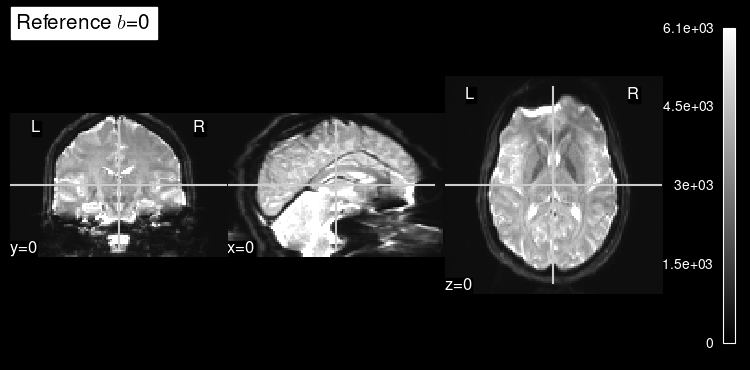

When calling plot_mosaic()

without any arguments, the b=0 reference is plotted.

This b=0 reference is a map of the signal measured without gradient sensitization, or in other words, when we are not measuring diffusion in any direction.

The b=0 map can be used by diffusion modeling as the reference to quantify the signal drop at every voxel and given a particular orientation gradient.